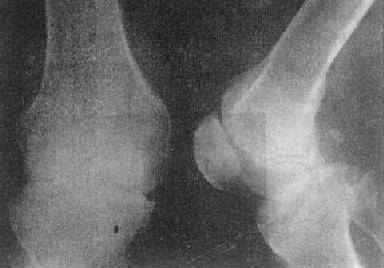

图2-1-14 关节破坏——膝关节结核

膝关节关节间隙变窄,关节面边缘有虫蚀状骨破坏

早期X线表现为关节囊和关节软组织肿胀,密度增高,关节间隙正常或增宽和骨质疏松。这些变化系因滑膜肿胀、增厚,形成肉芽组织和关节积液所致。可持续几个月到1年以上。因X线表现无特点,诊断较难。病变发展,滑膜肉芽组织逐渐侵犯软骨和关节面,首先引起承重轻、接触面小的边缘部分,造成关节面的虫蚀状骨质破坏,主要在边缘,且上下骨面多对称受累。由于病变首先侵犯滑膜,关节渗出液中又常缺少蛋白质溶解酶,关节软骨破坏出现较晚。因此,虽然已有明显关节面骨质破坏,而关节间隙变窄则较晚,与化脓性关节炎不同。待关节软骨破坏较多时,则关节间隙变窄(图2-1-14)。此时可发生半脱位。邻近骨骼骨质疏松明显,肌肉也萎缩变细。关节周围软组织常因干酪液化而形成冷性脓肿。有时穿破关节囊,形成瘘管。如继发化脓性感染,则可引起骨质增生硬化,从而改变结核以骨质破坏为主的X线表现。晚期,病变愈合,则骨质破坏停止发展,关节面骨质边缘变得锐利。骨质疏松也逐渐消失。严重病例,愈合后产生关节强直,多为纤维性强直,关节间隙变窄,但无骨小梁通过关节间隙。